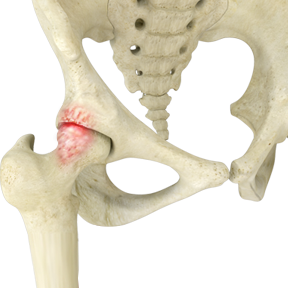

Hip Pincer Lesion with Labrum Tear

In the setting of FAI, a prominence of abnormal bone on the femoral head or the acetabulum causes the two bones to collide through an arc of motion. There are generally three types of impingement: CAM impingement (prominence on femoral neck), PINCER impingement (prominence of acetabular socket) and mixed impingement. These bone prominence can form from a variety of causes. Patients with painful FAI develop groin pain with hip motion. As the head rotates in the acetabulum, the labrum may become pinched and torn between the head and acetabulum.